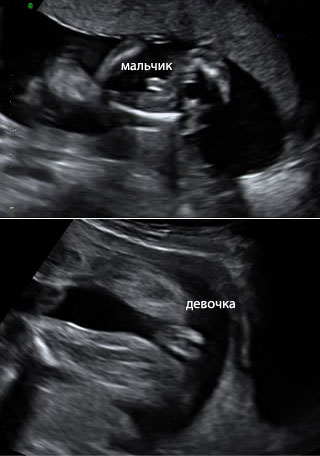

Ждём девочку)))))

между ножек:

А это мы на сроке 16,5)) Нам Мальчика пообещали)) Теперь Смотрю на Ваши фотки и точно понимаю что к чему)))

Поздравляю с принцессой 🙏🏻🙏🏻🙏🏻🌷🌷🌷 как же мне охото через недельку увидеть пистолет между ног, но думаю будут тоже 2 валика